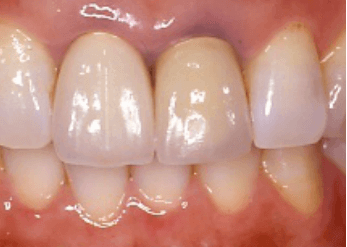

前歯2本の金属によるブラックマージン

前歯2本の金属によるブラックマージン 前歯4本オールセラミックスクラウン後

前歯4本オールセラミックスクラウン後